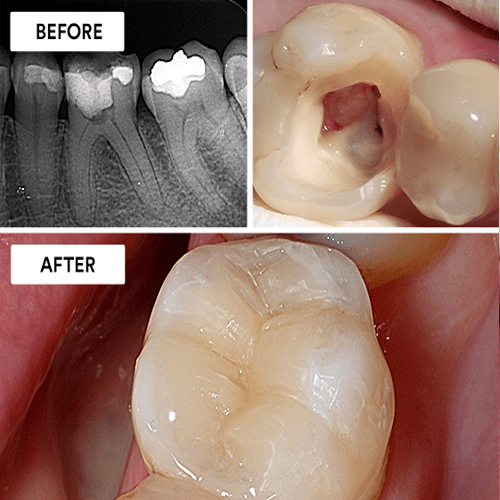

Our Root Canal Treatment is designed to eliminate infection from the tooth’s pulp, relieve pain, and restore dental health. For patients needing further intervention, we offer Re-Root Canal Treatment, which addresses complications from previous procedures. Additionally, our Post and Core services help rebuild and support teeth that are severely damaged, ensuring longterm stability.